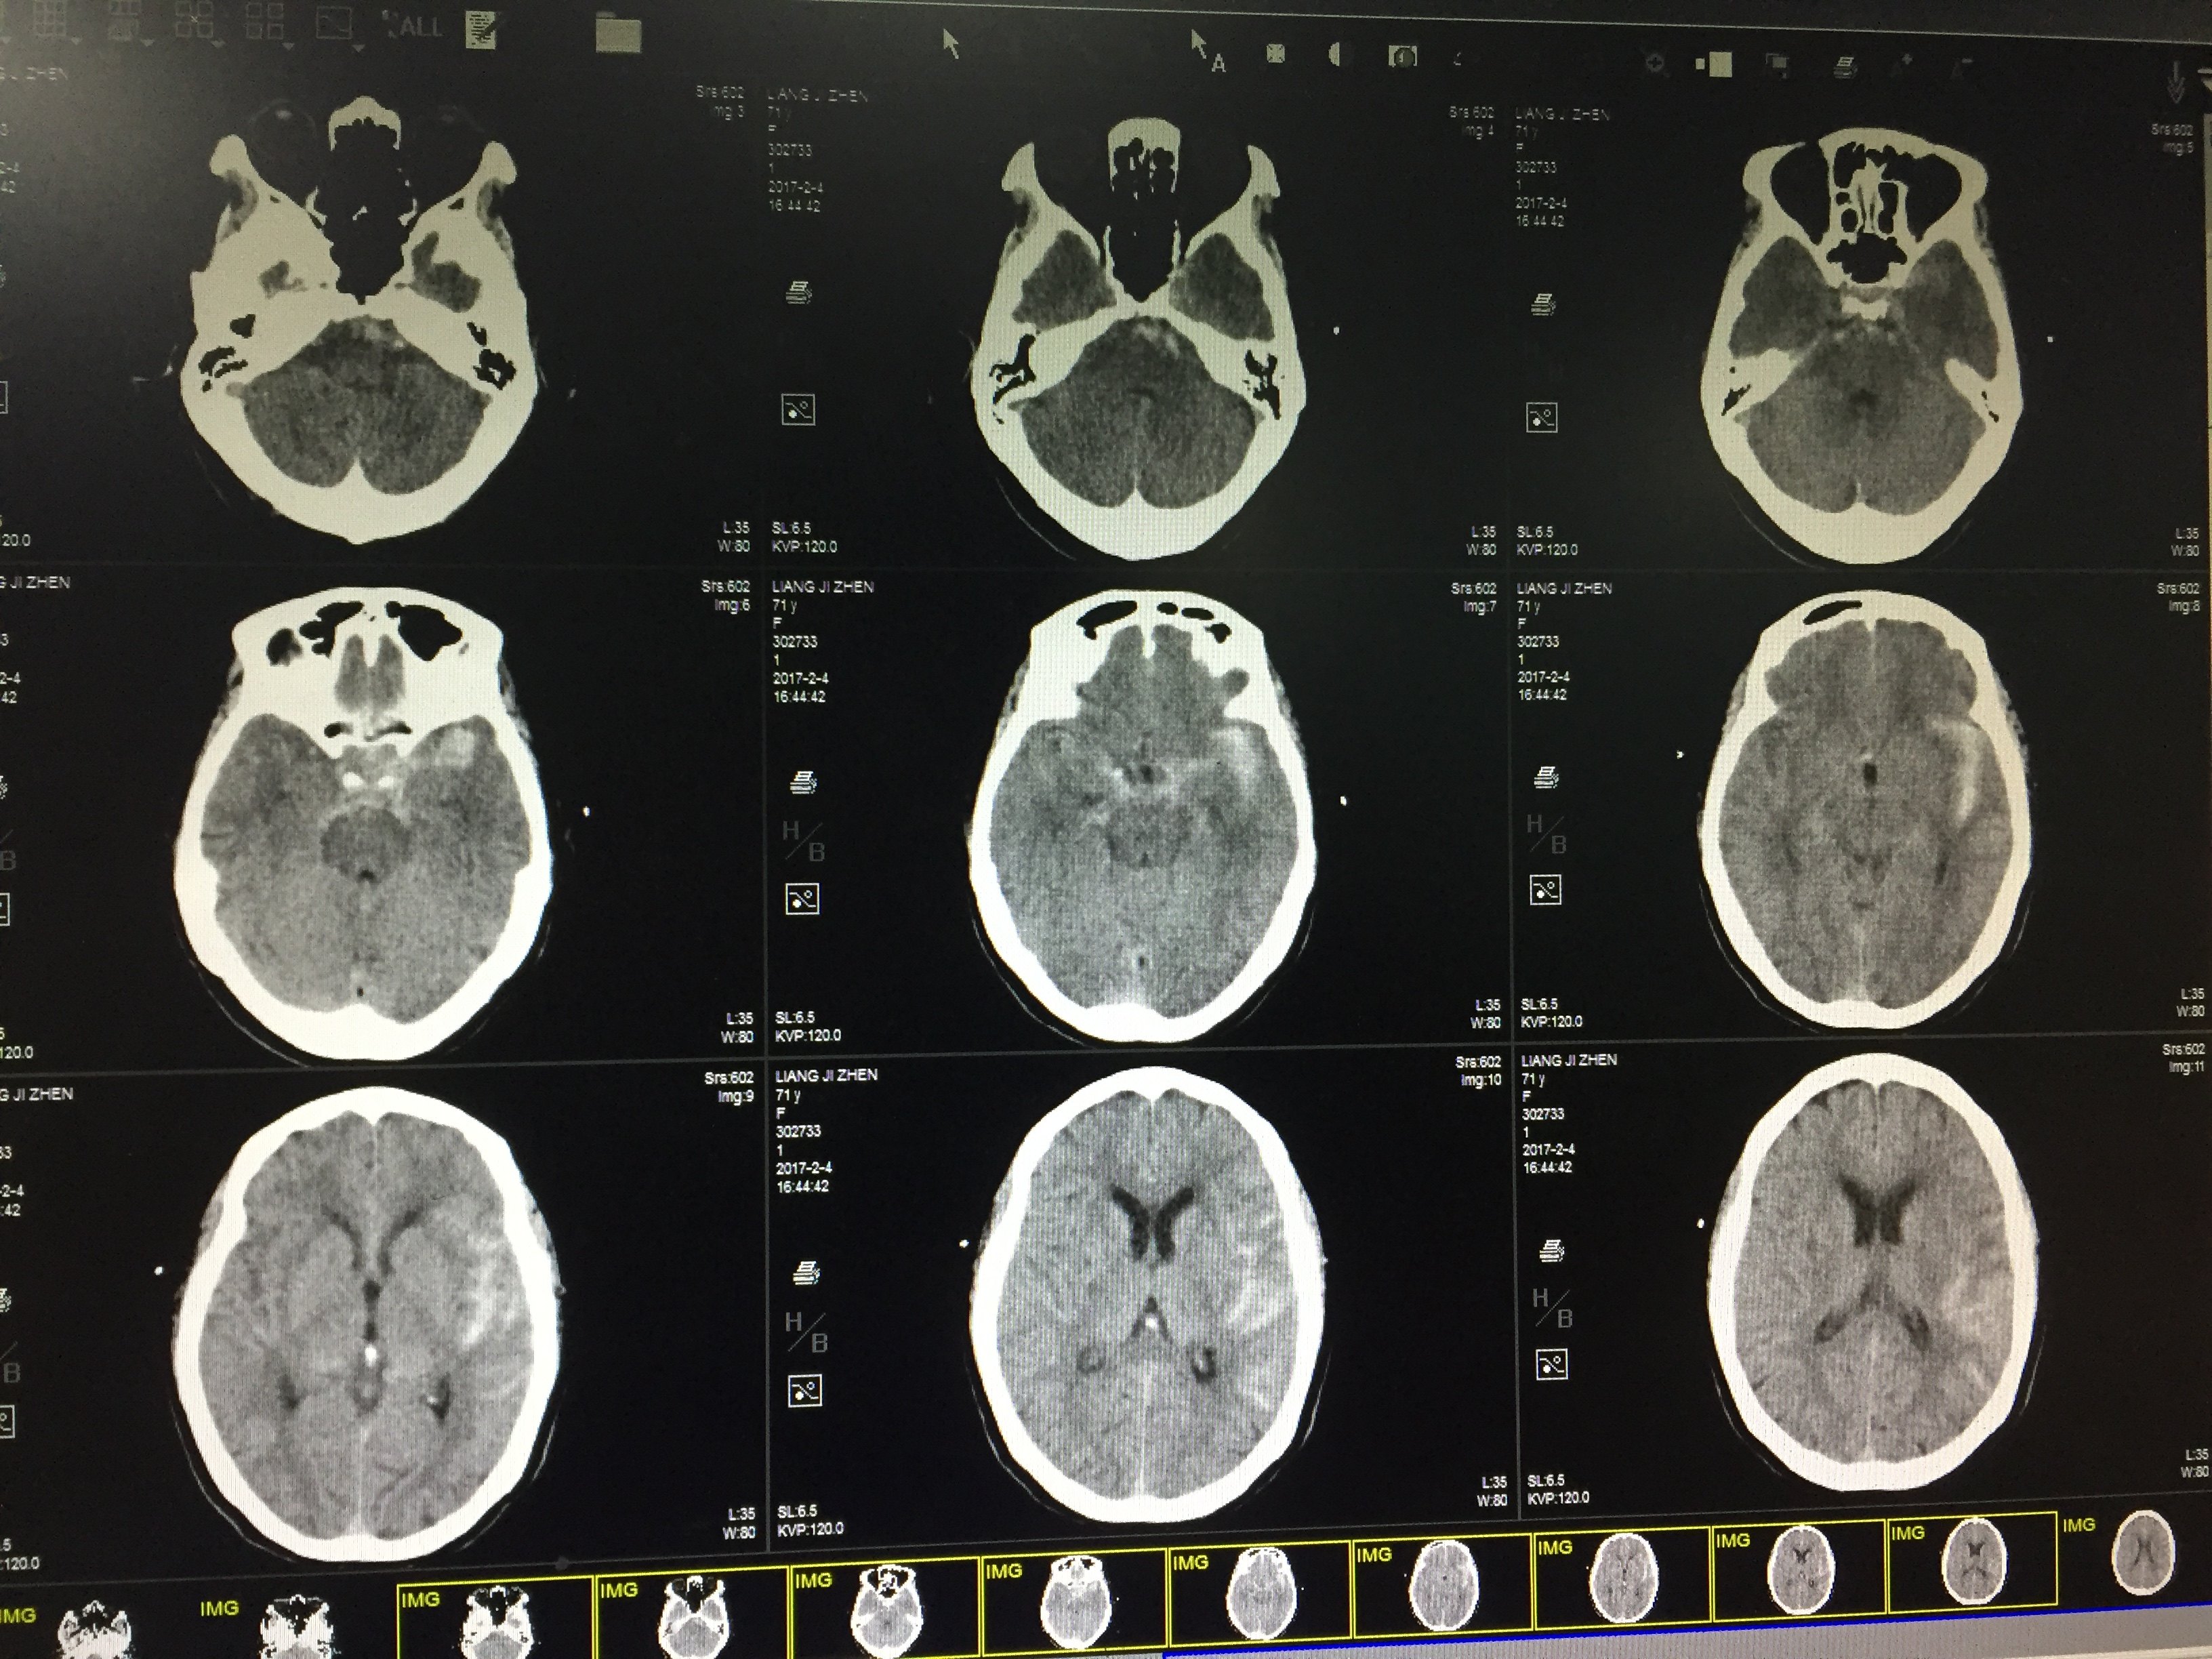

蛛网膜下腔出血ct图片

蛛网膜下腔出血ct图片,蛛网膜 结构图

蛛网膜下腔出血

颅内蛛网膜下腔出血,头颅ct可见明显的小血肿,出血点应该就在那里

ct蛛网膜下腔出血

蛛网膜下腔出血CT